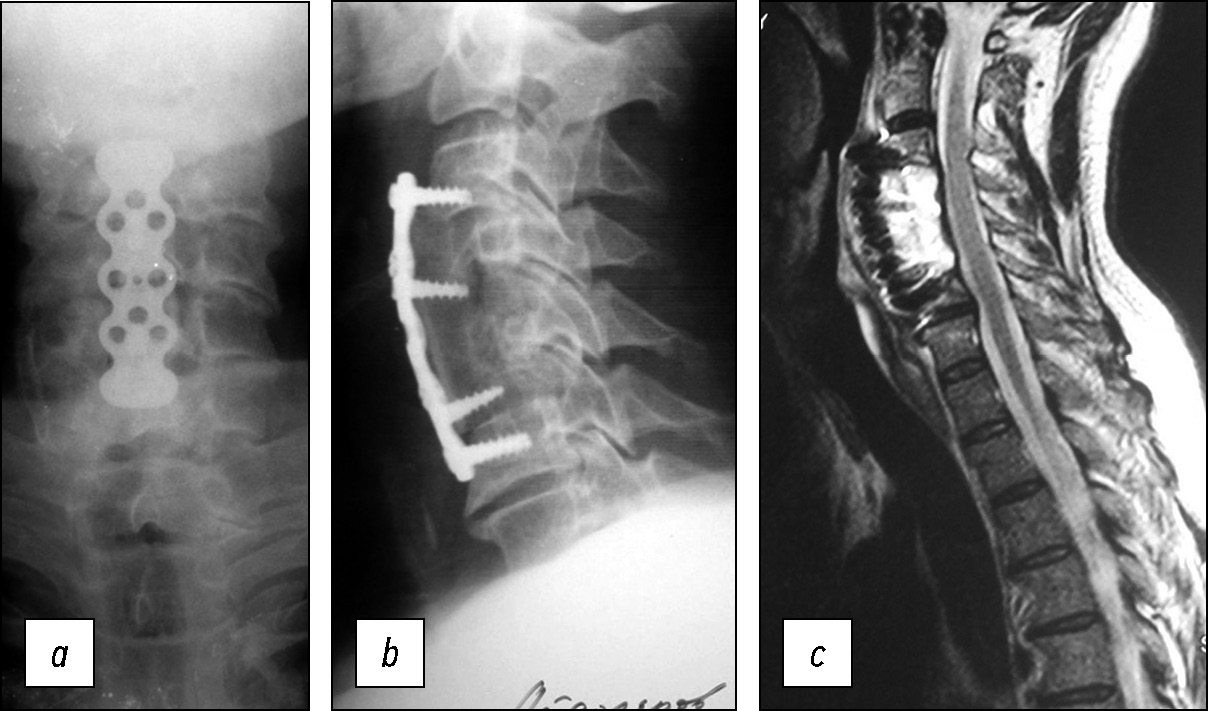

Пациенту проведены корпорэктомия С4-С5, удаление и дренирование эпидурального абсцесса, менинголиз, корпородез С3-С6 аутотрансплантатом, стабилизация пластиной «Atlantis». Интраоперационно длинные мышцы шеи и передняя продольная связка отёчны, гиперемированы, рыхлые. При удалении тел С4-С5 позвонков кость мягкая, легко удаляется ложкой. Твёрдая мозговая оболочка сращена с задней продольной связкой. На передней поверхности дурального мешка — рыхлая гранулема толщиной 3–4 мм с участками свободного гноя. Гранулема и гной удалены, выполнен менинголиз. Рана многократно промыта антисептиком. В ложе раны установлена приточно-отточная промывная система на 7 суток. Заживление раны первичным натяжением. На послеоперационных спондилограммах (рис. 3а, b) и МРТ (рис. 3c) стояние конструкции удовлетворительное, сдавления дурального мешка нет.

Рис. 3. Послеоперационные снимки: а, b — на рентгенограммах отмечается стабилизация сегмента С3-С6 аутокостью и фиксация цервикальной пластиной, с — на МРТ стеноз позвоночного канала устранён, компрессии спинного мозга нет.

Fig. 3. Postoperative cervical MRI and radiographic imaging data (a, b) show that the C3-C6 cervical segment stabilized with an autograft and an anterior cervical plate, с — the spinal canal stenosis has been resolved, and there is no evidence of spinal cord compression.

К моменту выписки больного тетрапарез значительно регрессировал. Пациент ходит самостоятельно, свободно. Температура тела нормальная, СОЭ снизилась до 22 мм/ч.